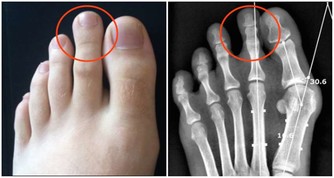

希臘腳(Greek Foot)則是第2根腳趾比其他還長,適合穿尖頭鞋,通常擁有這種腳型的人四肢修長,據說許多美女都符合希臘腳的特徵,有趣的是,紐約自由女神、希臘諸神雕像都是這種腳型。

但是擁有希臘腳真的是好事嗎?

美國研究指出,擁有希臘腳的人患拇囊炎、錘狀指以及背部疾病的風險更高。

因為多數人站立或行走時,腳趾中拇指所受的重量最多,但是對於希臘腳來說,則是第二腳趾會被磨彎、磨平,進而導致腳部疾病的發生。所以擁有希臘腳的人更要注意鞋子的版型,在選擇鞋子時一定要穿起來舒適而且符合腳型,否則會對健康有更多負面的影響喔!